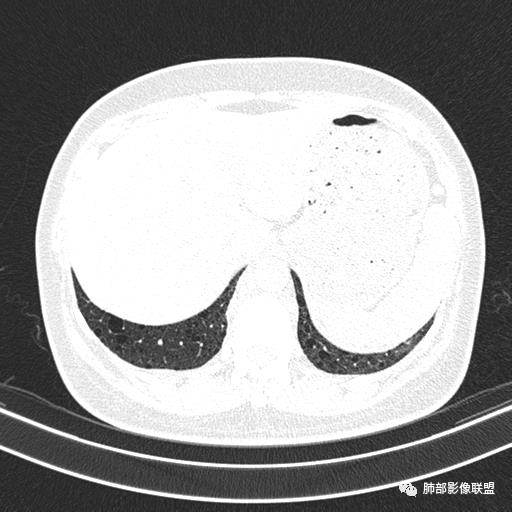

女,46,活动性气喘1年。苯吸入史半年。胸部CT:两肺弥漫囊腔,上至肺尖,下至肋膈角,形态类似小囊腔。考虑:LAM,鉴别LIP,BHD,PLCH等。

双肺弥漫大小不一薄壁含气囊腔,囊间肺组织正常,正常肺背景,肺尖肺底受累;青年女性,气喘,支持LAM

CT表现:双肺弥漫大小不等的薄壁囊腔,囊壁<2mm,外形规则,血管影多位于囊腔周围,囊腔之间肺组织正常,随着疾病进展到晚期,囊腔变大、增多,不可胜数,囊腔可融合成较大的囊,与肺气肿相似,形成间质性肺纤维化。部分病例可出现结节影。

临床诊断BHD综合征需要满足一个主要或两个次要标准。主要标准包括:1、皮肤上至少发现5个纤维滤泡瘤,至少1个组织学证实;2、致病的FLCN种系突变阳性。次要标准:1、多发肺囊肿,双侧基底部,有或无自发性气胸;2、肾癌,起病早(<50岁)或多灶性或双侧;3、 BHD综合征一级亲属。BHD主要影像表现特征:1、两肺内肺囊肿:80%以上的BHD患者会出现肺内囊肿,且倾向于基底部近胸膜下分布,特别是纵膈侧肺膜下,囊肿形状不规则、囊肿可大可小,肺内囊肿多毗邻肺下动脉或静脉近端,胸部CT上囊肿分布和特点对诊断有提示意义。2、继发自发性气胸:BHD患者发生气胸风险是正常人的5倍,BHD患者的气胸发生率约为 1/4,气胸复发率则高达59%。3、肾肿瘤:(常为双侧性、倾向于嫌色细胞组织学亚型)4、皮肤表现(为面、颈部纤维性毛囊瘤、毛盘瘤)